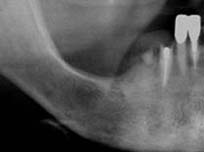

長い間不適合な入れ歯を使用していたために大量の骨を失ってしまいました。

特に下顎右の奥歯は骨の高さが不足しています。また上顎は上顎洞が大きくこのままではインプラントが埋入できません。【64才女性】

骨の高さがなく、このままでは神経を損傷せずにインプラントを埋入することは不可能です。 |

骨を約10mm垂直的に増やしています。 |

治療後のレントゲンをみると、奥の2本のインプラントはほとんど再生した骨だけで支えられていることがわかります。